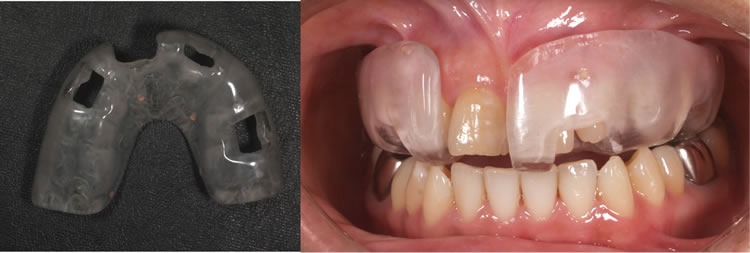

ラジオグラフィックガイド

ガイデッドサージェリー